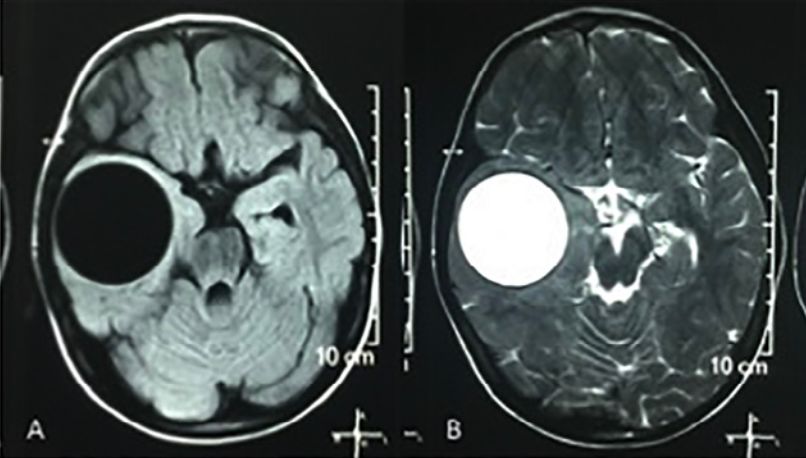

新生儿颅内海绵状血管瘤并囊性变1例 Medsci

有奖病例竞猜第152期答案丨癫痫小男孩脑子里长了个大水泡 雪花新闻